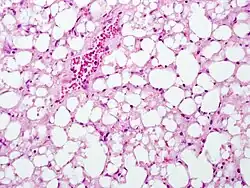

The second phase occurs between 24 hours and 72 hours following overdose and consists of signs of increasing liver damage. In general, damage occurs in liver cells as they metabolize the paracetamol. Hallmark pathology on liver biopsy includes regions of coagulative necrosis in zone 3 of the liver acinus, around the central venules, as these hepatocytes have higher concentrations of cytochrome P450 enzymes compared to zone 1 hepatocytes surrounding the portal venule of the acinus. Remaining viable hepatocytes frequently show ballooning injury and steatosis.[13] The individual may experience right upper quadrant abdominal pain. The increasing liver damage also changes biochemical markers of liver function; International normalized ratio (INR) and the liver transaminases ALT and AST rise to abnormal levels.[14] Acute kidney failure may also occur during this phase, typically caused by either hepatorenal syndrome or multiple organ dysfunction syndrome. In some cases, acute kidney failure may be the primary clinical manifestation of toxicity. In these cases, it has been suggested that the toxic metabolite is produced more in the kidneys than in the liver.[15]